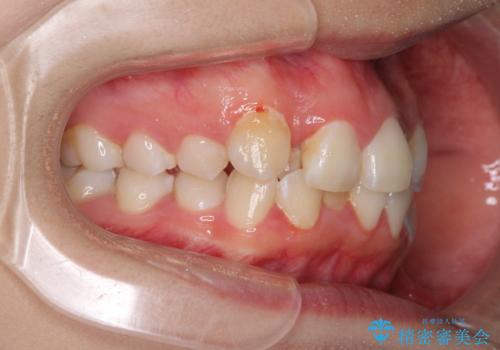

- 骨格的な咬み合わせのズレ、前歯のデコボコとクロスバイトを気にして来院された患者様です。

口元の突出感が若干あり口が閉じにくく、デコボコが強いため、上下左右の小臼歯計4歯を抜歯し、ワイヤー装置による矯正治療を行うこととしました。

また、舌の突出癖が強く、下顎前歯が前方に押し広げられる可能性が高いため、舌癖の改善を継続的に行うよう指示しました。